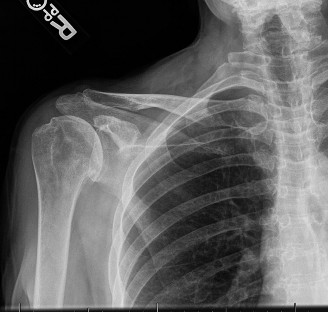

The correct answer is (E). Given that her rotator cuff has atrophied and has fatty infiltration to the point where there are equal parts fat and muscle, this is considered an irreparable rotator cuff tear. Repair should not be attempted because of poor outcomes following repair (see last two paragraphs of this discussion below). A reverse total shoulder arthroplasty is an alternative to repair that should be used in cases of massive, irreparable rotator cuff tears. It is a semi-constrained prosthesis that restores function in patients with massive rotator cuff tears by constraining a concave humeral cap inferior to a semispherical glenoid component (glenosphere). This creates an inferior force-couple and a fulcrum that replaces the stabilizing function of the infraspinatus maintaining a center of rotation around which the shoulder can move. This allows the deltoid to abduct and flex the shoulder without causing the humerus to migrate superiorly and about the acromion. In an elderly patient with a massive, irreparable rotator cuff tear (as in this patient), a reverse total shoulder arthroplasty is the procedure of choice.

It should be noted that reverse total shoulder arthroplasty is also the procedure of choice in patients with cuff-tear arthropathy (aka rotator cuff arthropathy). Characteristics of cuff-tear arthropathy include superior migration of the humerus due to a massive rotator cuff tear, glenohumeral joint destruction, subchondral osteoporosis, and humeral head collapse (see Fig. 2–17). A reverse total shoulder

arthroplasty in this case serves the purpose of eliminating pain caused by glenohumeral joint arthritis while restoring functional motion and is the procedure of choice in patients with cuff-tear arthropathy.

Figure 2–17_X-rays of a patient showing evidence of cuff tear arthropathy. The humerus is migrated superiorly, the glenohumeral joint is destroyed, there is subchondral osteoporosis, and the humeral head is collapsed. (From Ecklund KJ, Lee TQ, Tibone J, Gupta R. Rotator cuff tear arthropathy. _J Am Acad Orthop Surg. 2007;15(6):340–349.)